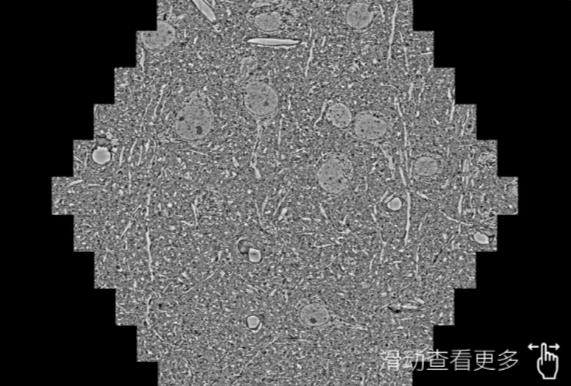

鼠脑切片。左图使用普陀蔡司普陀扫描电镜MultiSEM706对165μmx143pm面积区域成像,耗时仅需1.5秒。右图为鼠脑切片中30μm区域放大效果。样品由芝加哥大学B.Kasthuri提供。

使用蔡司高速普陀扫描电镜MultiSEM对1mm²人脑皮层组织进行高分辨成像,并对其中的各种细胞结构进行三维重构分析。左图展示了2x3mm²组织平面中锥体神经元的三维重构效果。右图显示了局部体积神经元三维重构。图像由哈佛大学chtman实验室提供,渲染图由D. Berger 制作。